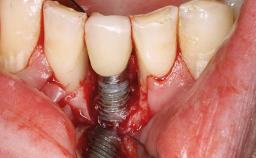

Removal of a Malpositioned Implant and Direct New Implant Placement with Simultaneous Contour Augmentation using GBR

A 35-year old female patient was referred to the Department of Oral Surgery and Stomatology at the University of Bern, Switzerland, for examination of an implant site that had exhibited clinical signs of slightly delayed wound healing. In addition, the referring clinician found no evidence for a facial bone wall when she raised a flap to gain access to the implant for abutment connection. Four months earlier, she had inserted a bone-level implant in a single-tooth gap, where the lateral incisor had been extracted due to a chronic periapical lesion on the mesial aspect of the root. Implant placement was combined with simultaneous bone augmentation using deproteinized bovine bone mineral (DBBM, Bio-Oss®; Geistlich, Wolhusen, Switzerland) and a collagen membrane (Bio- Gide®; Geistlich), followed by primary wound closure. The patient also provided the postsurgical radiograph that displayed the implant with a 3.5-mm healing cap.